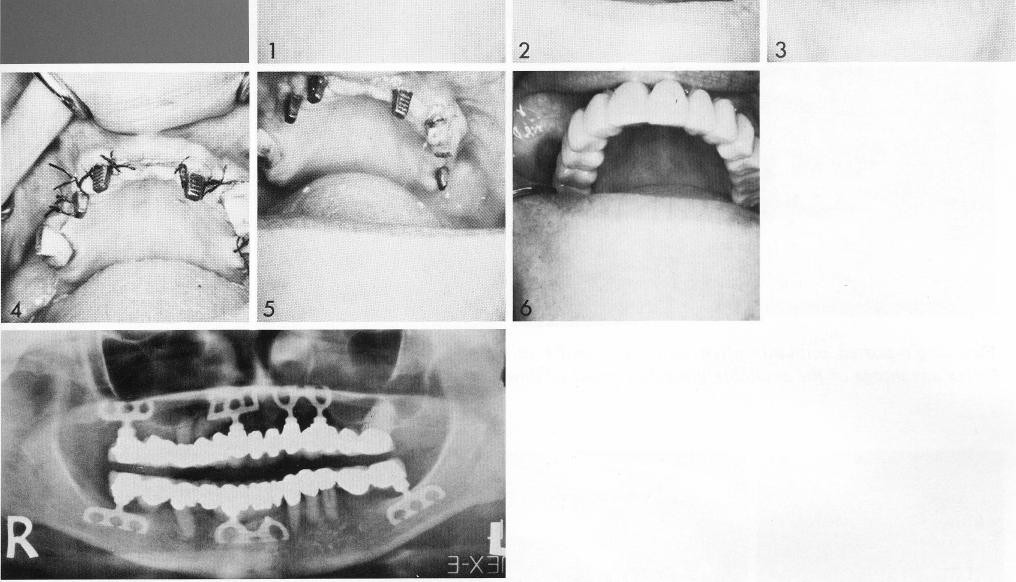

A knife-edge ridge was revealed when the tissues were reflected. This ridge was reduced (2) to accept bladevents (3). An open-socket bladevent was selected because its double posts helped counterbalance the singleposted bladevent and tooth combination. The recessed shoulder, not needed here to avoid an open socket—its original design intention, allowed the regrowth of more bone over the implant, an advantage in a narrow ridge situation. Posteriorly a bladevent was inserted in the maxillary tuberosity (4). In the mandible, one neck of an anterior bladevent was removed because the patient complained of sensitivity in the area.

1 A knife edge maxillary ridge revealed when the tissues reflected

2 Maxillary ridge reduced to accept bladevent implants

3 An open socket maxillary bladevent implant used